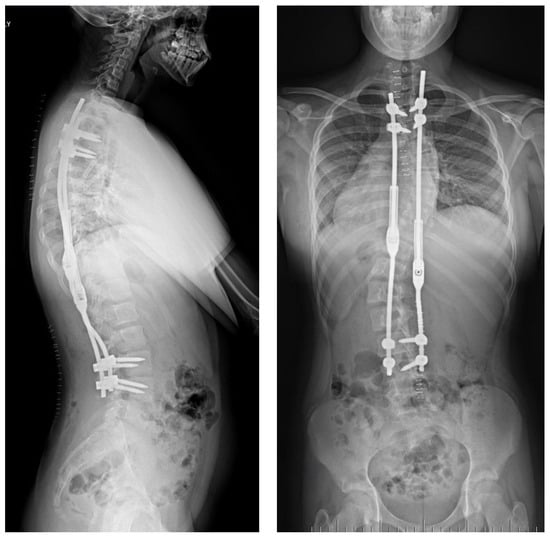

2.2. Example of Early-Onset Idiopathic Scoliosis

2.3. Example of Congenital Kyphosis